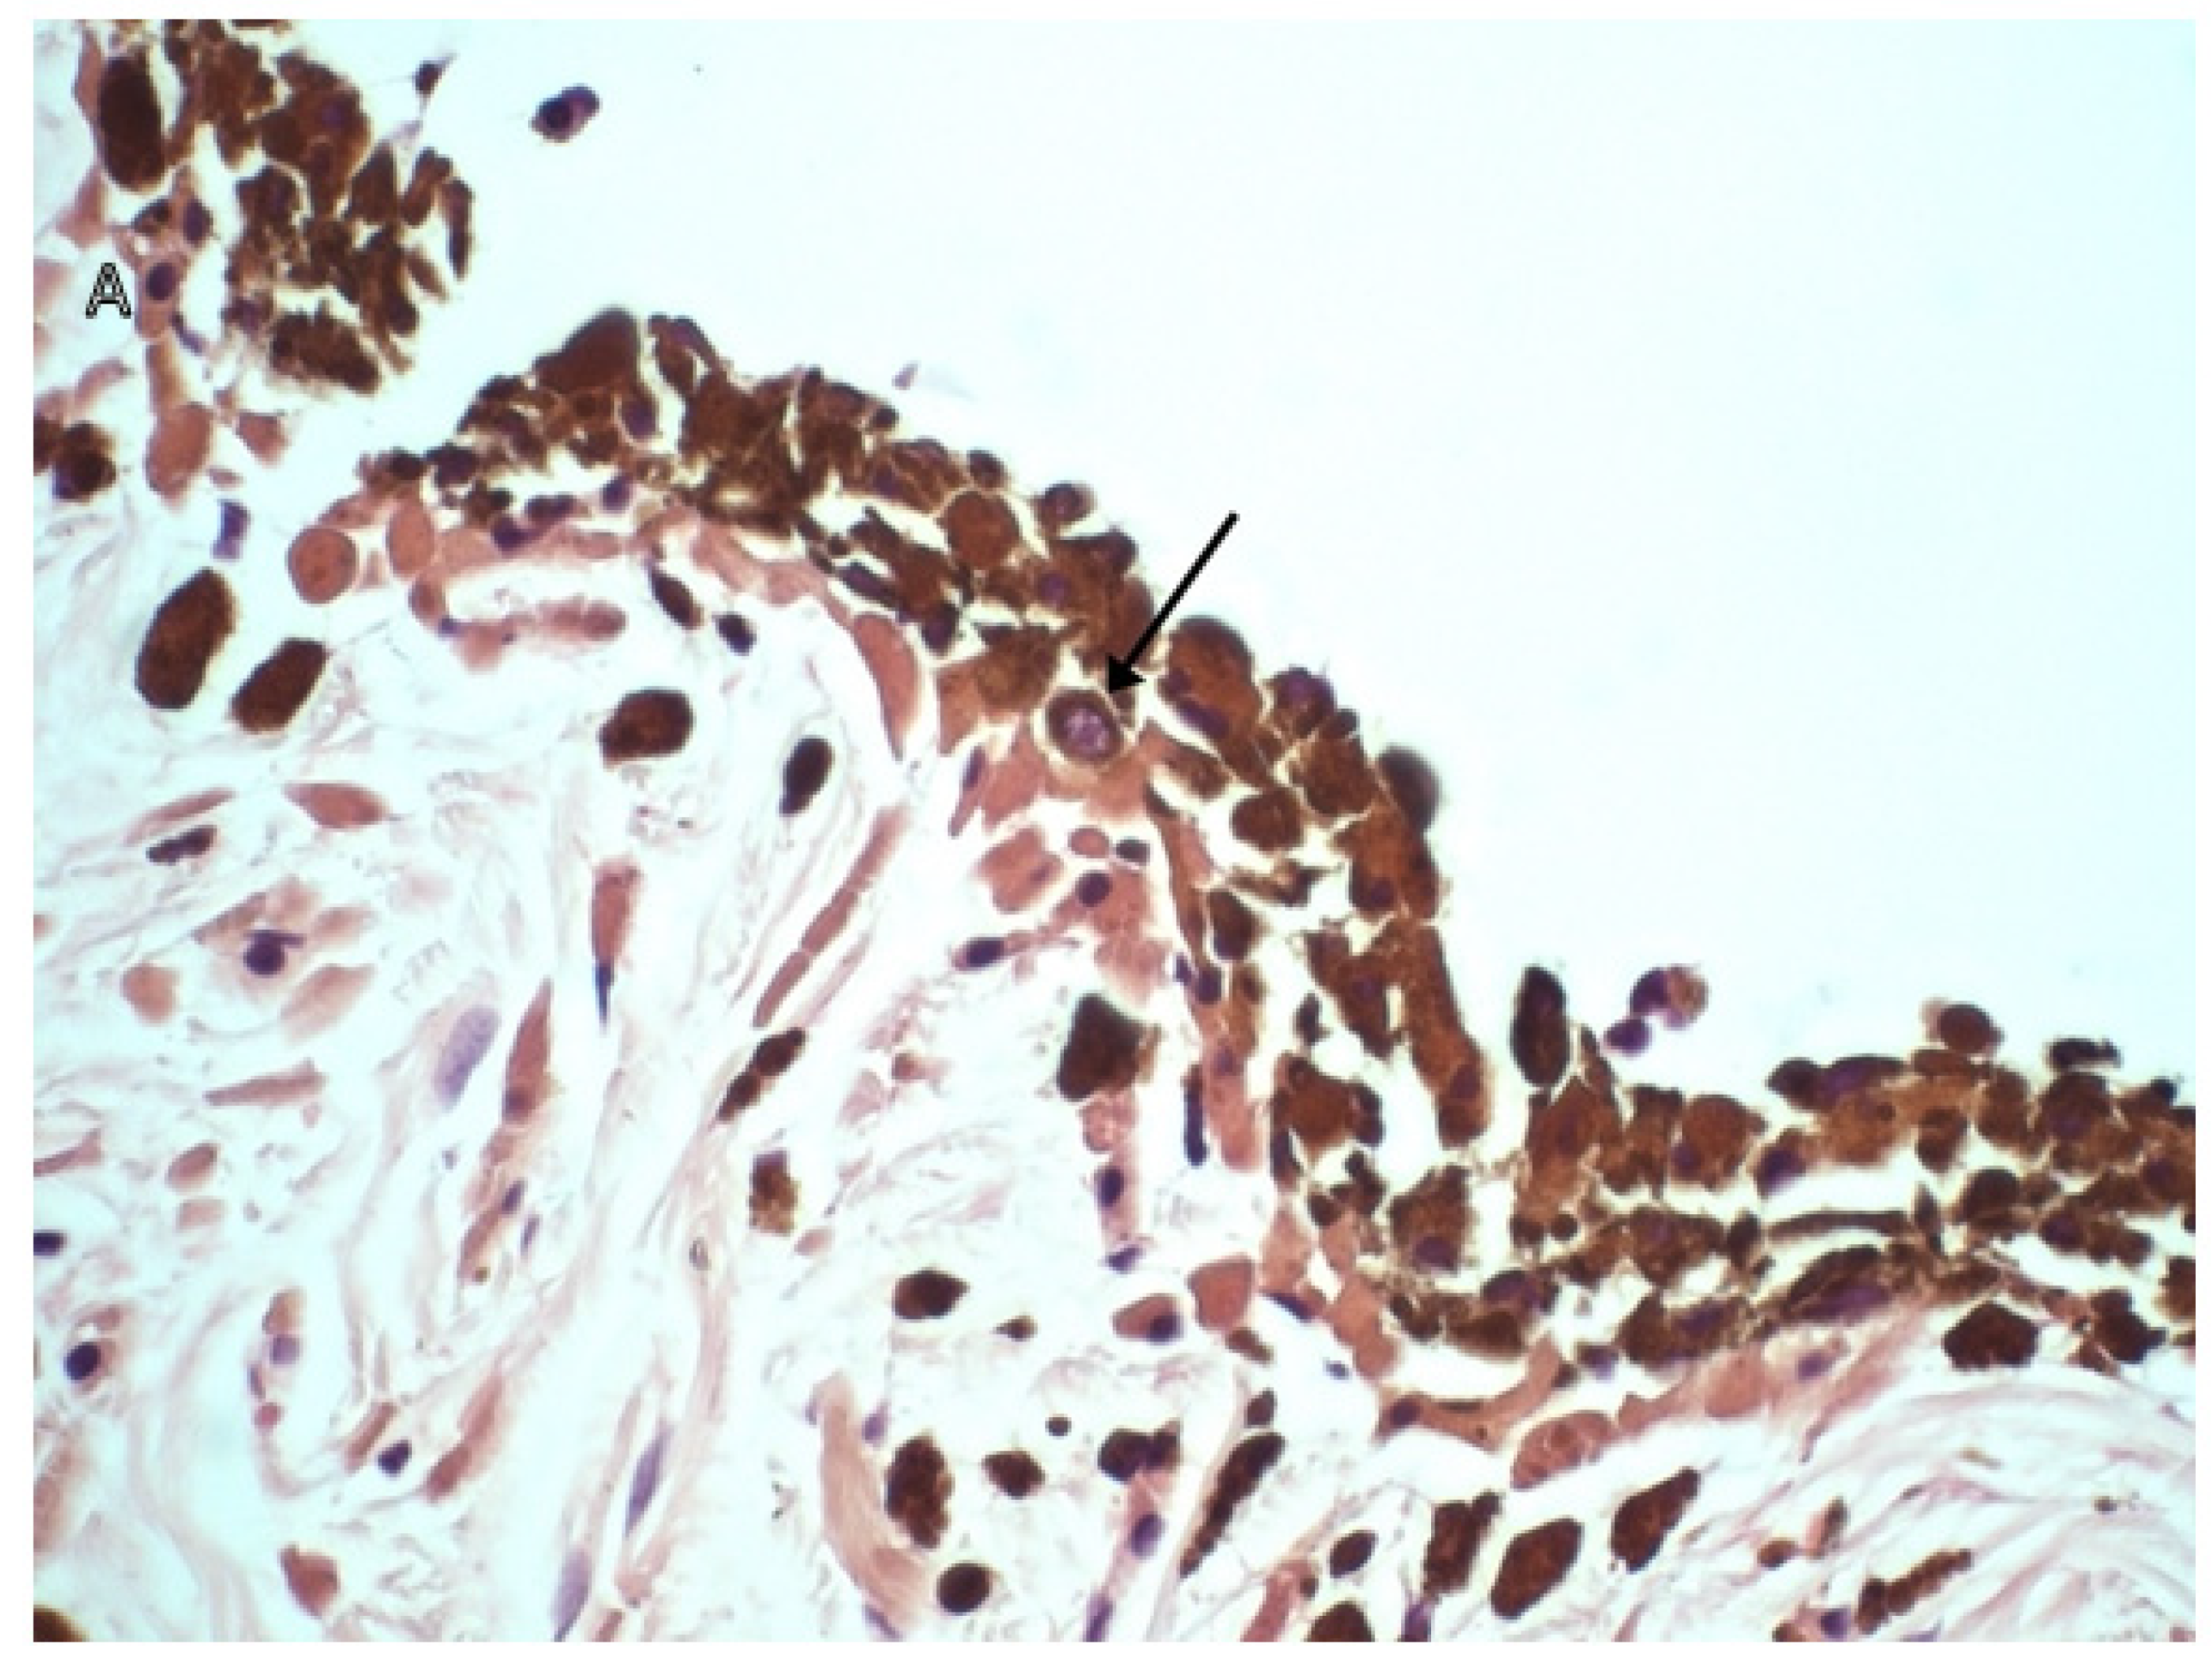

3.2. Immunohistochemical Markers

- Porcellato, I.; Silvestri, S.; Sforna, M.; Banelli, A.; Giudice, A.L.; Mechelli, L.; Brachelente, C. Tumor-infiltrating lymphocytes (TILs) in feline melanocytic tumors: A preliminary investigation. Vet. Immunol. Immunopathol. 2021, 242, 110337. [Google Scholar] [CrossRef] [PubMed]